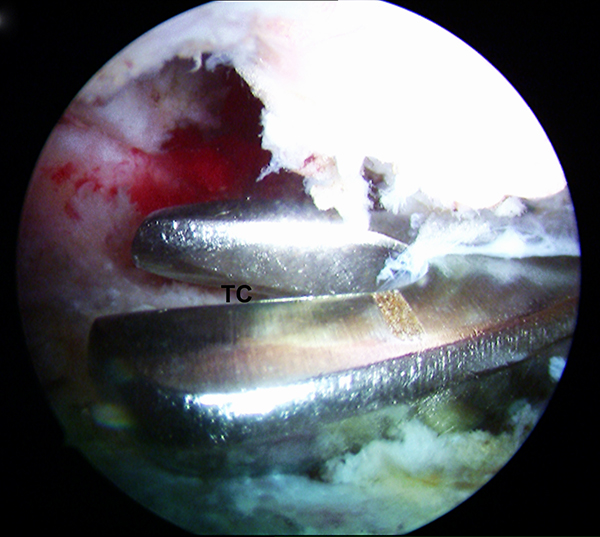

Abbildungen 14-17, Videos 4-5

Im nächsten Schritt erfolgt die arthroskopische Darstellung des Tuber calcanei (TC) mit Hilfe des Weichteilshavers und der Radiofrequenzsonde, bis eine gute Übersicht über die knöchernen Strukturen gegeben ist. Damit eine einwandfreie Orientierung und Platzierung des Zielgeräts gewährleistet ist, müssen alle störenden Gewebereste vollständig am Tuber entfernt werden. Zur besseren Übersicht kann es ggf. erforderlich sein, zusätzlich die tiefen paraachillären Zugänge zu verwenden (siehe oben). Unter arthroskopischer Sicht wird der Zielbügel über das posteromediale Portal eingeführt und auf der kranialen Prominenz des Tuber calcanei (TC) platziert. Arastru et al. 15 konnten in biomechanischen Untersuchungen am Kadaver nachweisen, dass die Fixation der FHL-Sehne möglichst weit posterior am Kalkaneus zu einem günstigen Hebelarm mit der besten Kraftentwicklung in der Plantarflexion führt.